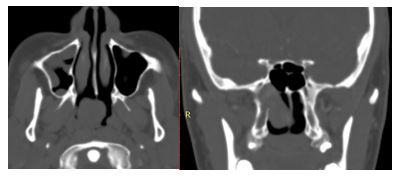

5. 05/2018. Masculino 22 años con obstrucción nasal de inicio gradual, epistaxis recurrente derecha, con masa fosa nasal ipsilateral que obstruye coana. TC con dependencia de pared lateral derecha. Clasificación IIA (Radkowski) I (Chandler). Se realiza angiografía y embolización de ramas de carótida externa ipsilateral, así como resección vía endoscópica con resección completa y buena evolución posquirúrgica a 3 meses, sin recurrencia.